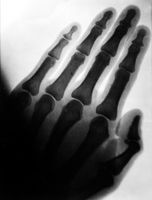

M0019298: X-ray of the hand of a healthy adult, c.1900

One of the earliest X-ray photographs to be made in the UK, from an original plate made by Sidney Rowland in 1896. It was presented to the Wellcome Historical Medical Museum in 1939 and accessioned in 1939 (accession number R791/1939). Related images: V0030063

1 photograph glass plate negative; 12 x 16.5 cm